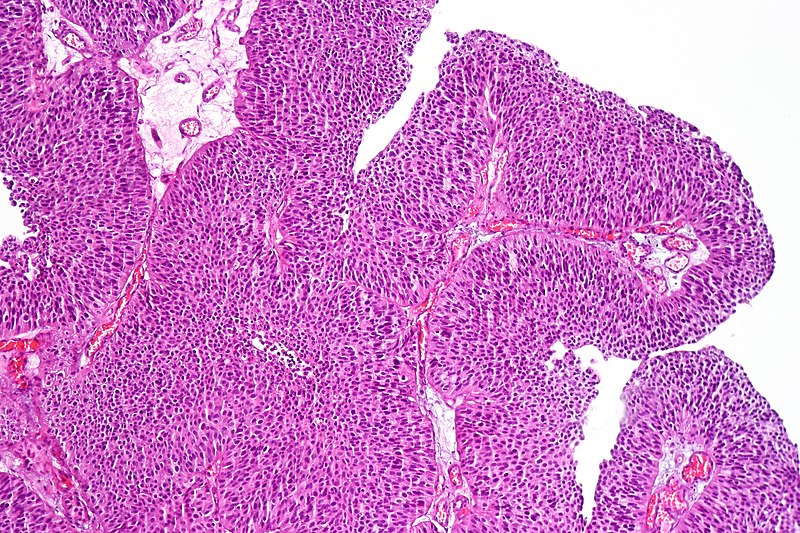

Urothelial carcinoma arises via two distinct pathways:

- Flat

- Papillary

Papillary urothelial carcinoma initially appears as a low-grade papillary tumor, advances to a high-grade papillary tumor, then invades, and is not linked to early p53 mutations.

Urothelial Carcinoma

Urothelial carcinoma is also known as transitional cell carcinoma.

The epithelial lining of the renal pelvis, ureter, bladder, or urethra is the source of this malignant tumor.

Urothelial carcinoma is the most typical type of bladder cancer.